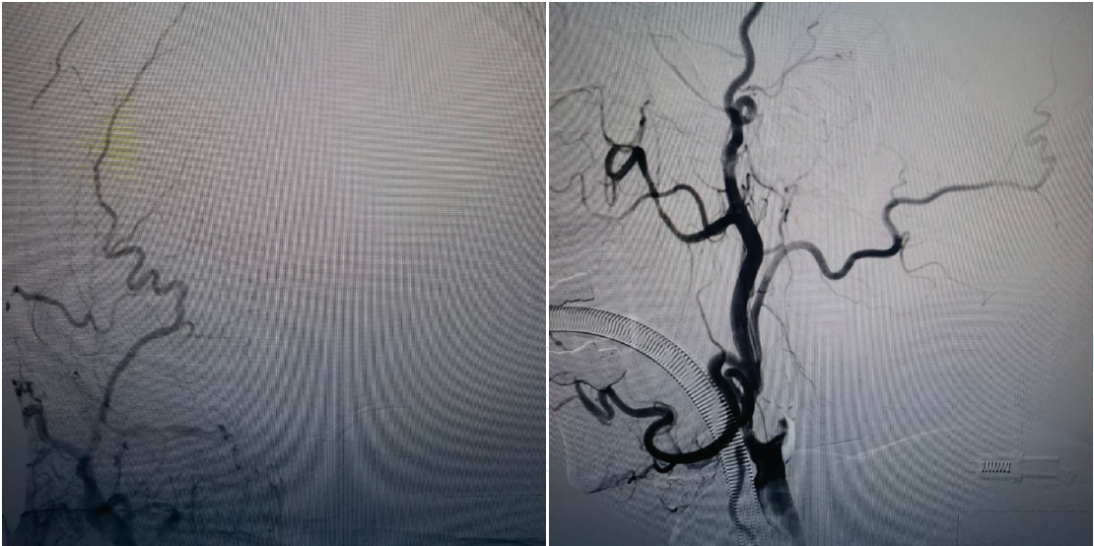

A microguidewire and microcatheter were carefully advanced through the occluded origin of the right ICA. Contrast injection through the microcatheter confirmed its position in the true lumen of the ICA. The microcatheter was exchanged for a long guidewire and withdrawn. A 2.5 mm balloon was used for pre-dilation at the occluded segment of the right ICA origin, followed by advancement of an 8F guiding catheter. A Zenith Aspiration Catheter was introduced coaxially and advanced along the ICA. Aspiration yielded a large amount of thrombus.

Post-aspiration angiography demonstrated good visualization of the right MCA and ACA.

To further manage severe stenosis at the origin of the right ICA, the aspiration catheter was withdrawn. A distal protection device was deployed through the 8F guiding catheter, which was then retracted to the common carotid artery. A peripheral balloon dilation catheter was advanced along the protection guidewire to the stenotic segment for angioplasty. After balloon dilation, a Wallstent was delivered along the protection guidewire and precisely deployed at the stenotic site. Post-deployment angiography showed good stent apposition, with a residual stenosis rate of approximately 20%. Antegrade blood flow and intracranial perfusion improved, achieving TICI grade 3 flow.

Postoperative Angiography

The right MCA, ACA, and their branch arteries were well visualized, with antegrade flow of TICI grade 3 and no signs of acute vascular occlusion.